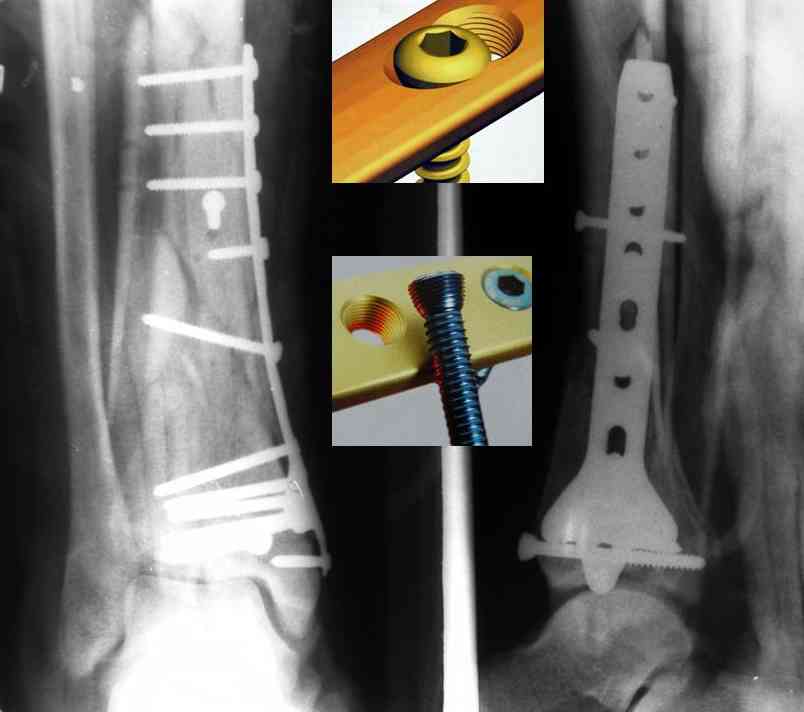

Это типичный перелом пилона, который надп лечить только открыто.Извини те что опоздал к обсуждению, но даже если вы уже оперировали больного по Илизарову это даже лучше.Посылаю картинки.

Посмотрим вроде прошло если понравится напишите расскажу как это сделать.По принципам АО кстати при поступлении сначала восстанавливают длину малоберцовой кости фиксируют пластиной 1/3 трубки потом накладывают аппарат наружной фиксации и через 7-10 дней открыто восстанавливают большеберцовую кость.С уважением Дрягин

На рентгенограммах типичный перелом пилона по типу С-3. есть опыт до 100 открытых опреаций у нас в клинике. 20 примерно в год. Принцип один -все внутрисуставные переломы нуждаются в открытой репозиции и внутренней стабильной фиксации. При поступлении КТ не надо, так как получается только нагромождение костей. Истинной картины нет. Главное восстановить длину малоберцовой кости - это ключ к успеху. При поступлении меньше всего надо думать о сосудистых расстройствах, т.к. сама операция и репозиция даже сначала частичная даёт улучшение сосудитых нарушений. Причём очень быстро. Операция в 2этапа. При поступлении доступ позади наружной лодыжки, причём обязательно. После этого репозиция малоберцовой кости и фиксация пластиной 1/3 трубки под винт 3,5. Дренаж и любой аппарат наружной фиксации. Затем после спадения отёка на 5-7-10 день аппрат снимается и дугообразный разрез спереди от медиальной лодыжки 10-12 см. Главной чтобы расстояние между 1 и вторым разрезом было не меньше 7-8 см. Тогда не будет некрозов лоскутов. Таранная кость используется как матрица на неё укладываются отломки и фиксируются пицами. Ренг-контроль. Отломки лежат все отдельно, но ничего не высыпется. При переломах С-3 всегда нужна костная пластика (из крыла). Фиксация пластиной лист клевера простой или LCP. Гипс не нужен. Дренаж до 48 часов. Операция длится 3-4 часа обязательно без жгута. Посылаю примерно такой же случай.